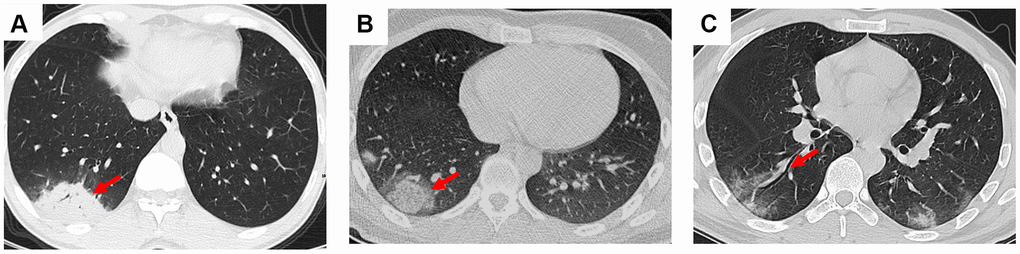

In this study, we presented some common and typical radiology changes (Figures 1 and 2). The most common radiology characteristic seen on the CT was ground-glass opacity (64/66, 97%). Most ground-glass opacities were characterized by scattered and bilateral lesions (Figure 1A and 1B). The CT scans of 15 (15/66, 23%) patients shown crazy paving (Figure 1C), and consolidation was observed in 7 (7/66, 11%) patients (Figure 2A). In addition, air bronchogram sign (47/66, 71%, Figure 1D), pleural traction (29/66, 44%), interlobular septal thickening (11/66, 17%), and halo sign (3/66, 5%, Figure 2B) were also observed (Table 2). Bronchiectasia was observed in the right lower lobe of one patient with bilateral ground-glass opacity (Figure 2C).

Figure 2. Consolidation, halo sign, and bronchiectasia in the CT scans of COVID-19 pneumonia patients. (A) Consolidation accompanying air bronchogram sign was found in the right lower lobe of a 46-year-old male patient; (B) Halo sign was observed in the right lower lobe of a 18-year-old male patient; (C) Bronchiectasia was observed in the right lower lobe of a 30-year-old male patient with bilateral ground-glass opacity. Typical lesions were marked with red arrows.